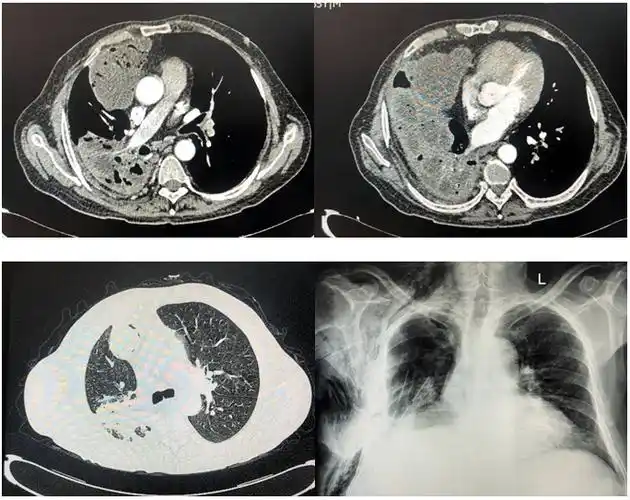

胸部,腹部ct回报:肝脏,右肺及腹腔,盆腔多发巨大囊性病灶,符合包虫病